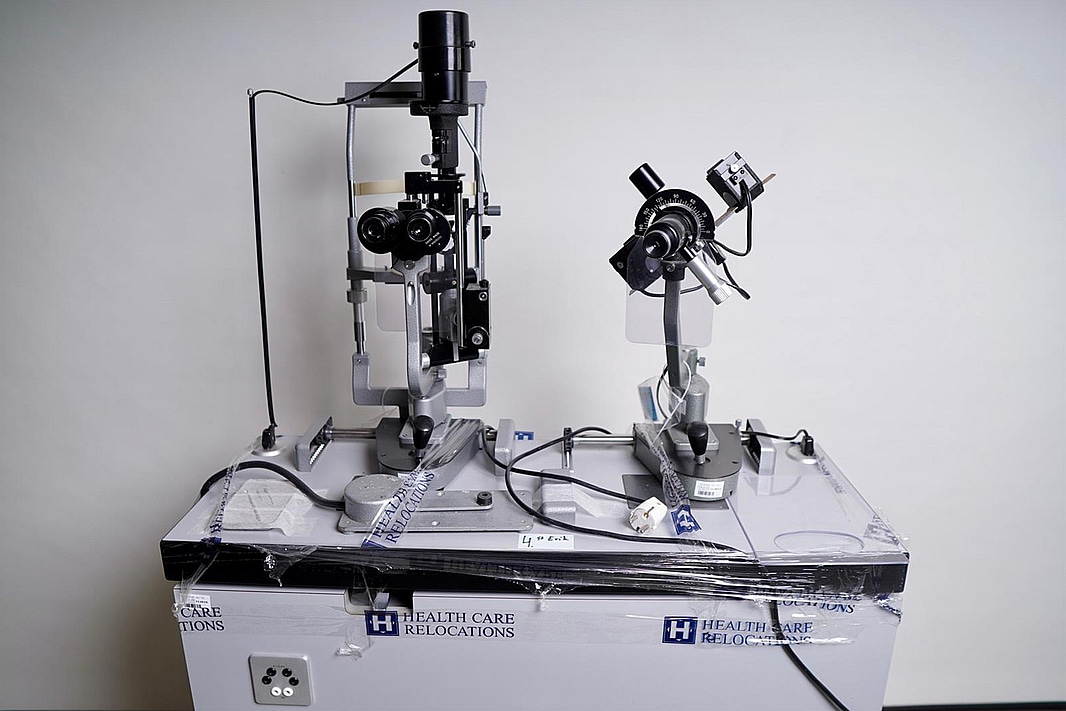

Optiker utrustning, undersökningsbord. Spaltlampa Haag-Streit 900.

Not allowedSpaltlampa Haag Streit 900

The Haag –Streit BM 900 has been the standard in modern slit lamp microscopy for almost 50 years – and still is! Over 100,000 professionals all over the world who own a BM 900 agree that it was the best investment they ever made for their practice. The BM 900 is the “classic” slit lamp for the eyecare professional concerned with both the anterior and posterior segments.

A convergent, stereoscopic microscope offering short observer to patient distances and “workhorse” 10 and 16 X magnifications (with standard 10 X eyepieces – optional eyepieces with other magnifications are available – see “Accessories”). PD and optical correction are both finely adjustable to give easy viewing with none of the eye fatigue so often associated with use of the slit lamp.

The Cross Slide Mechanism incorporated into all Haag –Streit slit lamps, has both vertical and horizontal movements controlled by our patented joystick. Perfection in design, materials and construction allow these movements to be made smoothly and effortlessly without any wrist or finger strain – and to continue so for the very long lifetime of this classic slit lamp.

The illumination system has the brightest (600,000 Lux) illumination available in a slit lamp providing a tilting, rotating slit up to 8 mm in length and width.

Tilting is extremely important to good posterior segment observation. All filter and slit controls are conveniently situated for ease of use and, as with the cross slide mechanism, have silky smooth, effortless movement. The slit mechanism, on of those “differences inside”, is a masterpiece of engineering in itself, affording faultless precision in both shape and movement. Imaging A “through the eyepiece” digital adaptor for the BM 900 is available.